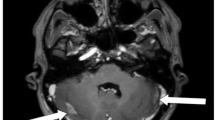

Each microbleed was segmented using a 2D recursive region growing algorithm from a seed indicated by an experienced observer (Fig. 1). The connected 2D segments were combined to generate a 3D segmentation of the microbleeds. For each microbleed, the location of the center of mass and size in voxels and mm’s was recorded, as well as the microbleed count for each individual survivor. The coordinates for the center of mass of each microbleed were transformed into a standard brain reference space (MNI space) by first normalizing the SWI data set into template space using Statistical Parametric Mapping v12 (SPM 12)32. The resulting transformation was then applied to the coordinates of the center of mass. The coordinates were then mapped to Talirach space using the icbm2tal transform technique as previously described33. Location labels were generated for each microbleed based on the coordinates of the center of mass using the taxonomy maps developed by Brainmap.org.34,35. Microbleeds were assigned to one of the following locations: frontal lobe, parietal lobe, temporal lobe, occipital lobe, anterior lobe cerebellum, posterior lobe cerebellum, medulla oblongata, pons, sub-lobar (region defined to fill the remainder of volume within the hemisphere, such as the insular cortex) and midbrain. Locations were combined for left and right side. Additionally, microbleeds were categorized as located in grey matter or white matter, unless in the sub-lobar and brainstem regions where they were classified as mixed.

Example of a region of interest selection performed by the region filling algorithm. The arrow highlights the same microbleed in both the Susceptibility Weighted Minimum Intensity Projection image (SW mIP) (A,C) and corresponding Filtered Phase image. (B,D) Note detection and measurements could be accurately captured near areas of air induced susceptibility artifacts (orange arrow) using this method. (C,D) (Images are displayed in radiological convention).